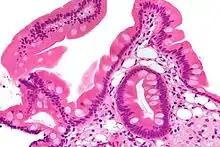

| Low magnification micrograph of Whipple's disease showing the characteristic foamy appearing infiltrate of the lamina propria. Duodenal biopsy. H&E stain. | |

Endoscopy of the duodenum and jejunum can reveal pale yellow shaggy mucosa with erythematous eroded patches in patients with classic intestinal Whipple's disease, and small bowel X-rays may show some thickened folds. Other pathological findings may include enlarged mesenteric lymph nodes, hypercellularity of lamina propria with "foamy macrophages", and a concurrent decreased number of lymphocytes and plasma cells, per high power field view of the biopsy.

Diagnosis is made by biopsy, usually by duodenal endoscopy, which reveals PAS-positive macrophages in the lamina propria containing nonacid-fast, Gram-positive bacilli.[4] Immunohistochemical staining for antibodies against T. whipplei has been used to detect the organism in a variety of tissues, and a polymerase chain reaction-based assay is also available,[4] which can be confirmatory if performed on blood, vitreous fluid, synovial fluid, heart valves, or cerebrospinal fluid.[9] PCR of saliva, gastric or intestinal fluid, and stool specimens is highly sensitive, but not specific enough, indicating that healthy individuals can also harbor the causative bacterium without the manifestation of Whipple's disease, but that a negative PCR is most likely indicative of a healthy individual.[4]